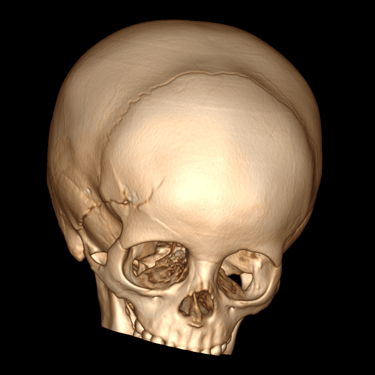

La fractura craneal es una lesión que puede producirse tras un traumatismo craneoencefálico, con riesgo de comprometer el cerebro y las estructuras intracraneales. Los síntomas incluyen dolor local, edema, hematomas y, en casos graves, alteración del nivel de conciencia. La tomografía computarizada (TC) es el estudio de elección para su diagnóstico, ya que permite identificar con precisión el trazo de fractura, desplazamientos óseos, hemorragias asociadas y la afectación de senos venosos o base de cráneo. Un diagnóstico temprano mediante TC es esencial para definir la conducta terapéutica y prevenir complicaciones neurológicas potencialmente graves.